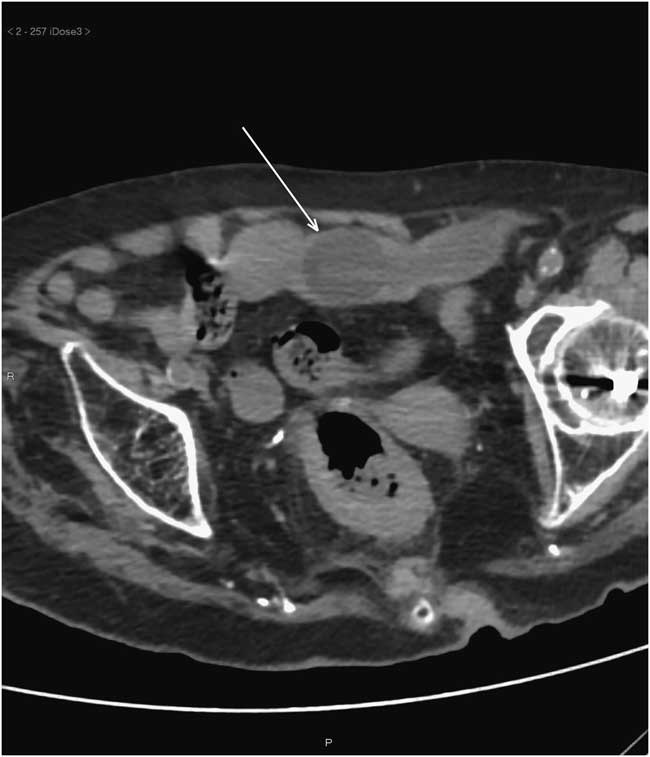

A 94-year-old woman with a history of advanced dementia presented to the emergency department (ED) from her nursing home with a urinary tract infection (UTI) and abdominal pain. On presentation, her vital signs were normal, but mild abdominal distention was found and she vomited once. Her past medical history was also significant for hiatal hernia, bilateral hip fractures five years prior, permanent urinary catheter, and recurrent UTIs. She was on no medications. Although the referral letter said she was being fed by percutaneous endoscopic gastrostomy (PEG) tube, the ED team noted immediately that no tube could be found. Plain flat x-ray revealed partial small bowel obstruction, but the tube could not be visualized. An urgent CT was ordered which identified the inflated balloon and indicating its position in the terminal ileum (Figure 1). The patient was admitted. A percutaneous needle puncture of the balloon failed. Laparotomy was refused by the patient’s substitute decision-maker. She died a few days later.

Figure 1 Single axial image of abdominal CT scan without contrast demonstrating an inflated Foley catheter (arrow) lodged in the terminal ileum. Proximal to it, moderate bowel loop dilatation was present (not shown).